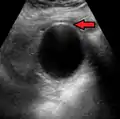

استخدام الموجات الفوق صوتية هو أهم خطوة من خطوات التصوير الإشعاعي ومن ثم التصوير المقطعي.

Mild gallbladder wall thickening of 3.5 mm in a person with acute cholecystitis as seen on ultrasound

Acute cholecystitis as seen on ultrasound. The closed arrow points to gallbladder wall thickening. Open arrow points to stones in the GB